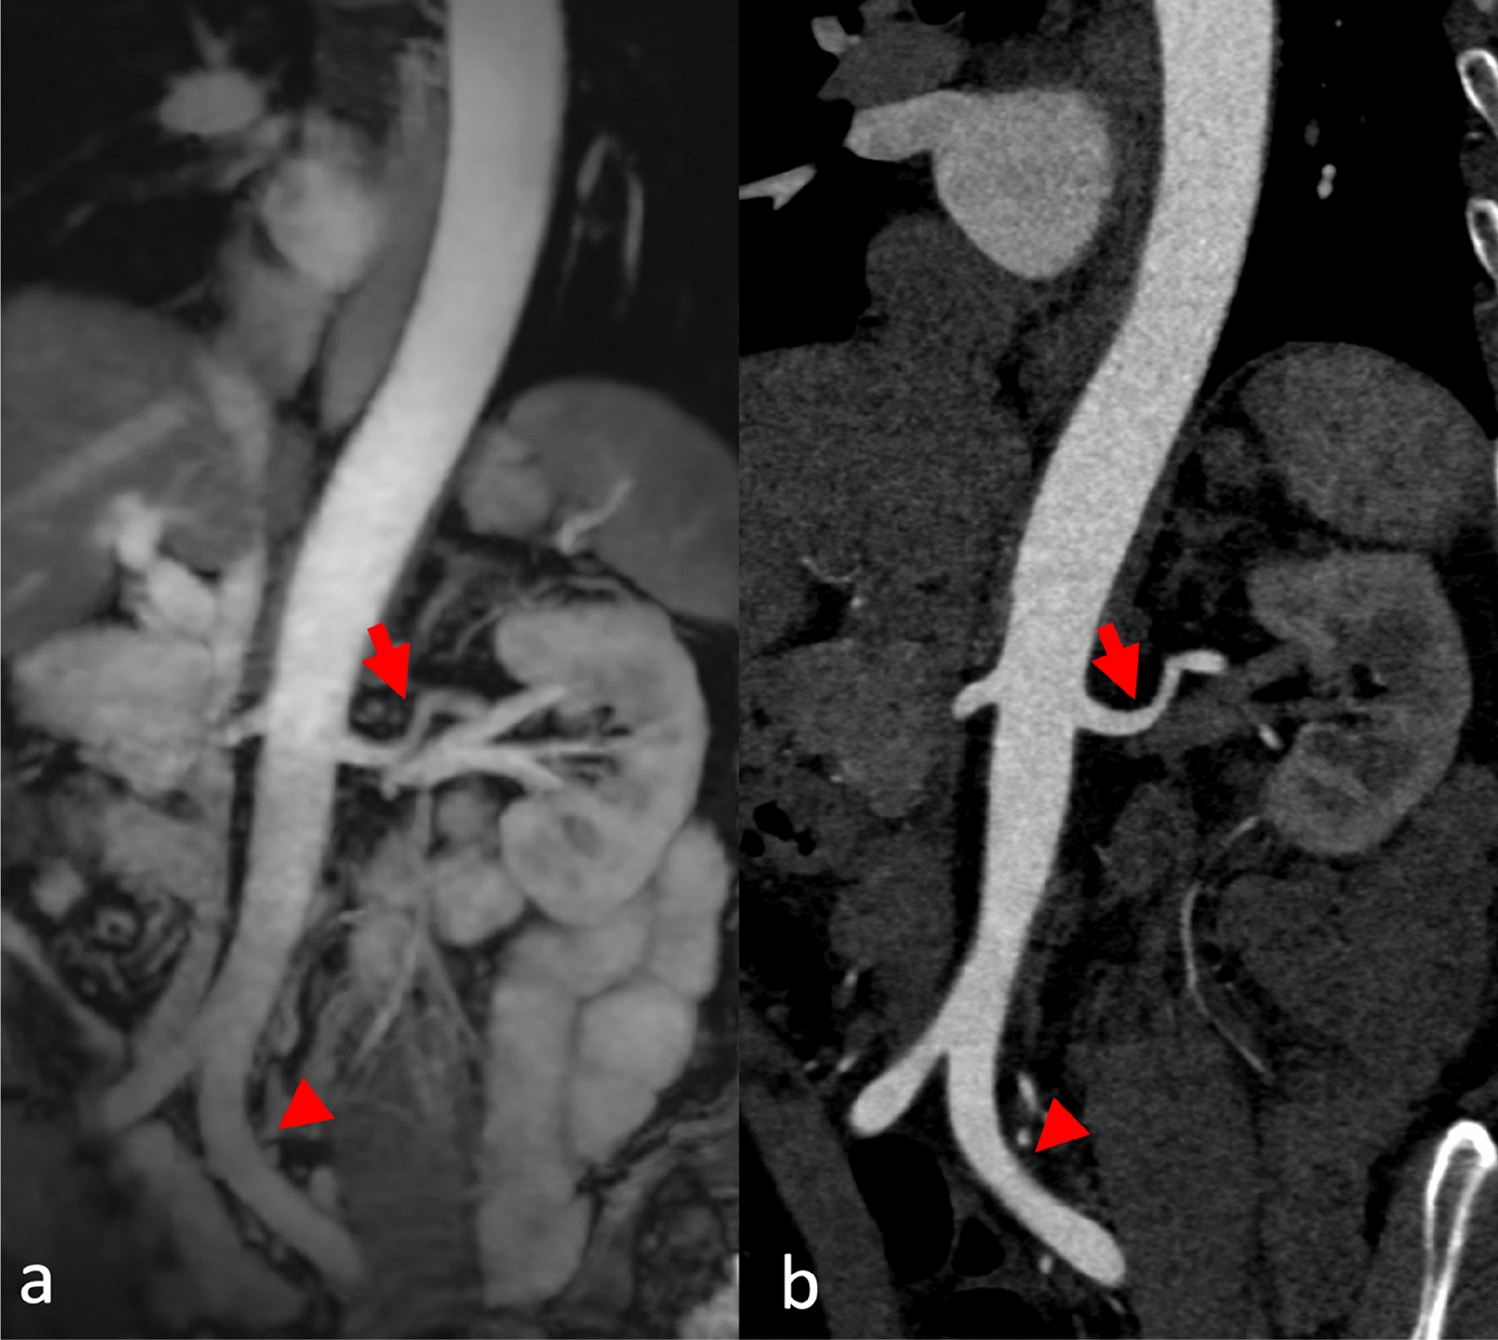

Fig. 4

A female patient had experienced multiple collapses on the day of admission and presented to the Emergency Department with cold, clammy skin and severe thoracic pain. The aortic CT scan ruled out dissection. Coronal reformation of MRA (a) and CTA (b) of the abdominal aorta to the iliac arteries (arrowhead). Excellent depiction of smaller vessels, such as the left renal artery (arrow)